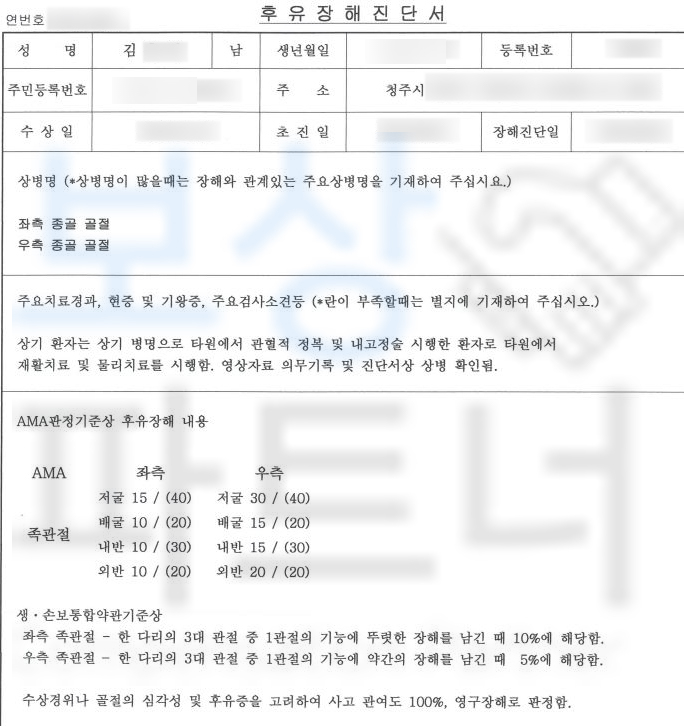

실제 진단서를 보실까요?

종골의 골절, 폐쇄성 S9200 진단을 받았습니다. 위 병명으로 김@@님은 관혈적 정복 후 금속 고정술 시행받았고 10주간 석고 고정 진단을 받았습니다. 먼저 일하다 다친 사고이기에 의무 가입인 산재 보험에서 치료비와 일을 못하는 기간에 대해 보상을 받을 수 있습니다.

뿐만 아니라 산재 보상 외에도 김@@님의 개인보험에서도 후유장해 보상을 도와드렸습니다. 김@@님의 보험증권과 영상CD를 함께 살펴보며 기본적인 상담을 도와드렸고 이후 저희는 주치의를 통해 후유장해진단서 발급을 받으려고 하였습니다.

하지만 주치의는 매번 달라지는 보험약관에 대해 생소할 뿐만 아니라 자신의 치료에 대해 장해를 진단하는 것이 쉽지 않은 부분인데요, 보상파트너는 공신력있는 타병원의 **전문의를 통해 **김@@님의 상황을 전달한 뒤 장해진단서를 발급받을 수 있었습니다.

양발의 종골골절 총 15% 지급율 입니다 물론 보험사에서는 내무자문을 시행하며 약 한달간의 분쟁이 오갔지만 결국 저희가 처음 청구한 15%, 후유장해 보험금 1,200만원 지급받을 수 있었습니다.